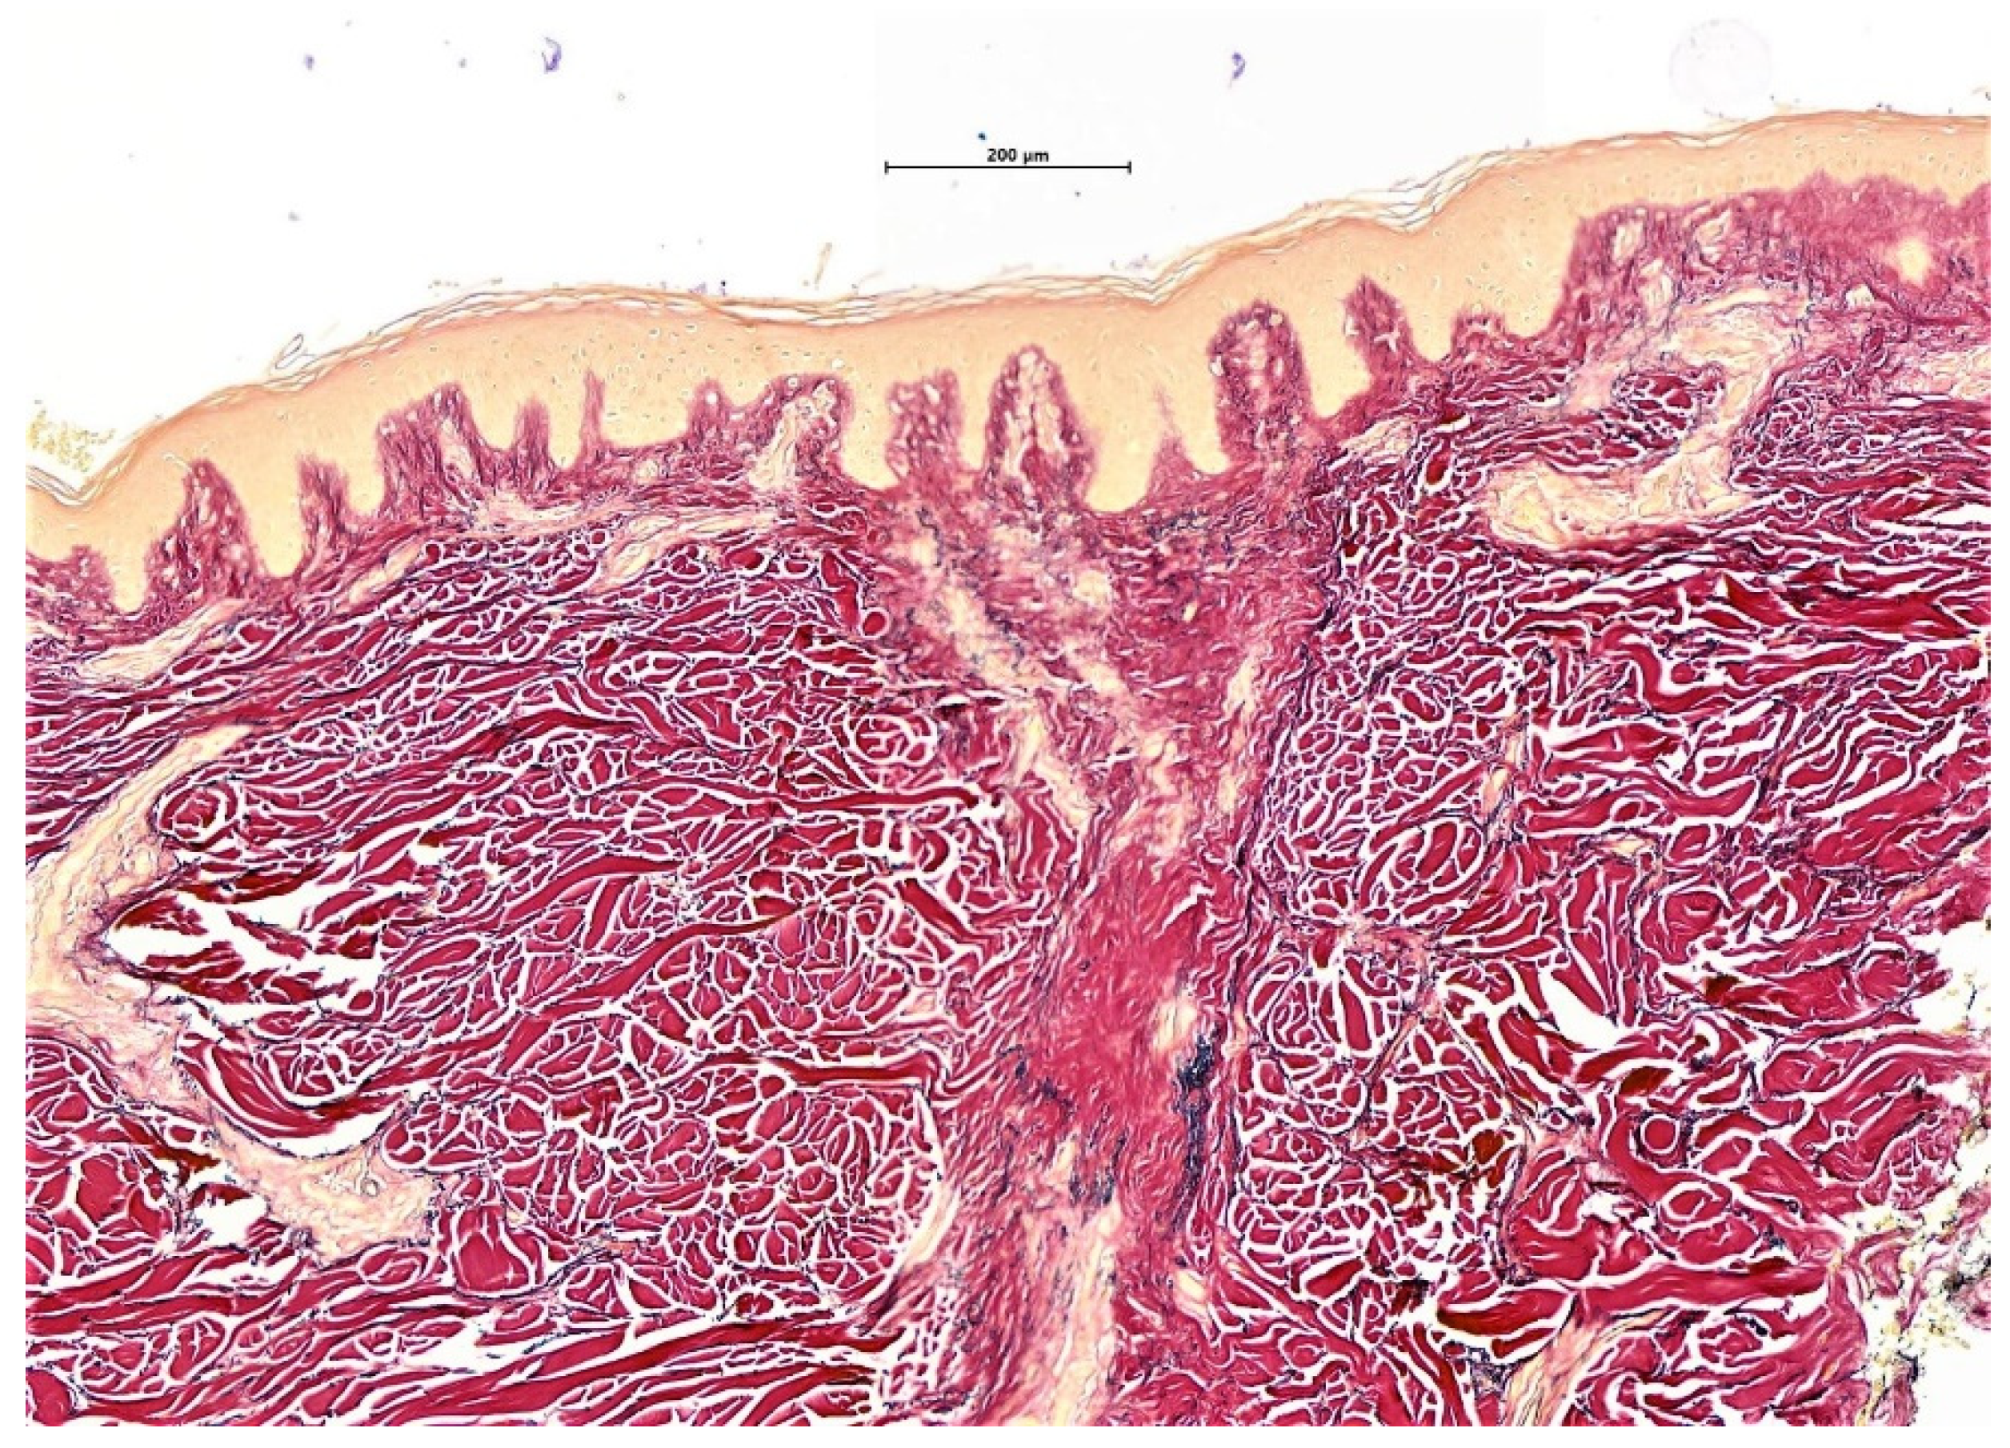

- Fung, M.A.; Sharon, V.R.; Ratnarathorn, M.; Konia, T.H.; Barr, K.L.; Mirmirani, P. Elastin staining patterns in primary cicatricial alopecia. J. Am. Acad. Dermatol. 2013, 69, 776–782. [Google Scholar] [CrossRef]

- Elston, D.M.; McCollough, M.L.; Warschaw, K.E.; Bergfeld, W.F. Elastic tissue in scars and alopecia. J. Cutan. Pathol. 2000, 27, 147–152. [Google Scholar] [CrossRef] [PubMed]

| Elastic tissue staining | Loss of elastic tissue and the elastic sheath in a superficial wedge-shaped scar | Broad scar throughout the dermis and destruction of the elastic sheath surrounding the fibrous tracts | Hyalinization of the dermis with increased and thickened elastic fibres. Broad fibrous tracts with preserved elastic sheath | Superficial wedge-shaped scar with late diffuse dermal scar/fibrosis |